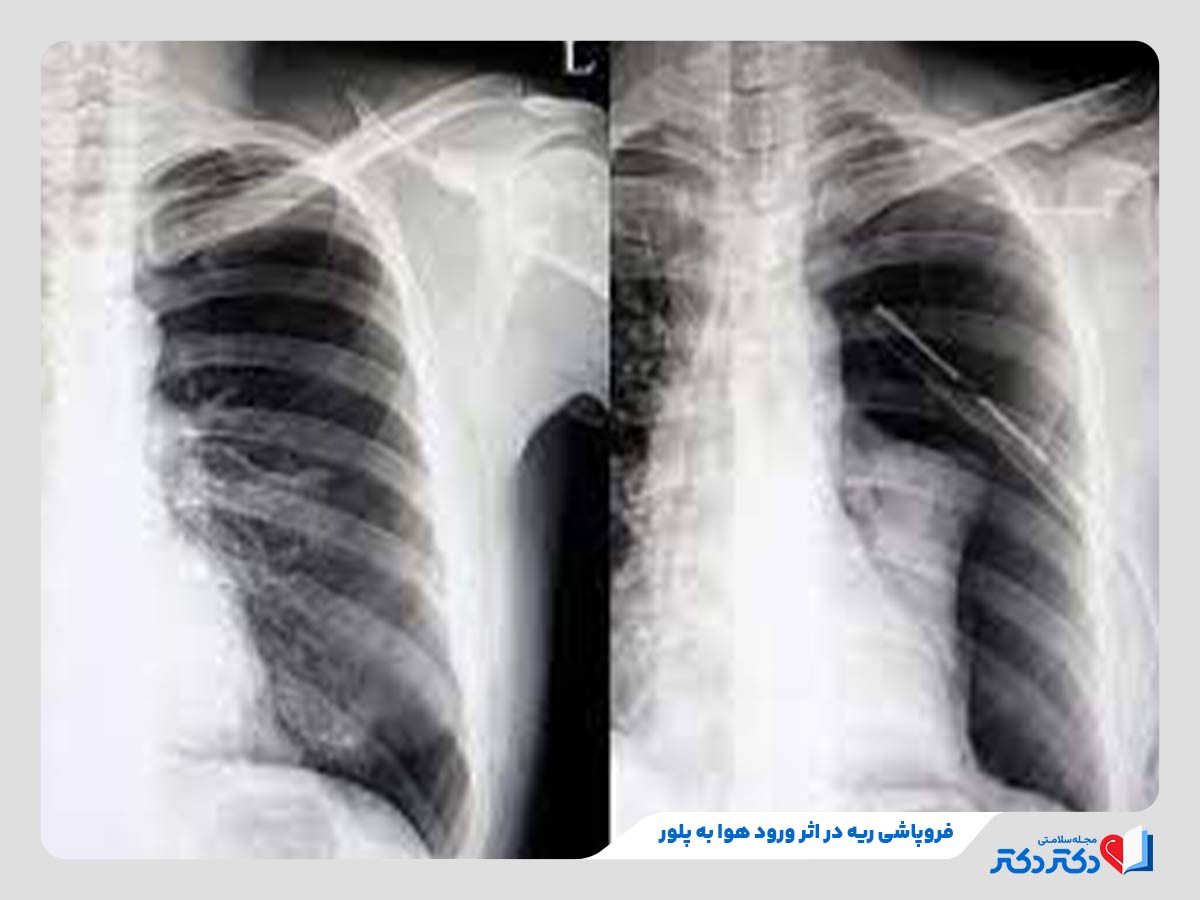

بیماریهای پلور ریه

پلورا، لایه نازکی است که سطح ریه و دیواره داخلی قفسه سینه را میپوشاند. بیماریهای پلور علتدرد قفسه سینه و اختلال در حرکت ریه خواهد شد. مثالهایی از این نوع بیماری ریوی به شرح زیر است:

- افیوژن پلور: تجمع مایع بین دو لایه پلورا که طبق معمول در تاثییر نارسایی قلبی یا پنومونی رخ میدهد.

- پنوموتوراکس: ورود هوا به فضای پلور که علتفروپاشی ریه میبشود.

- مزوتلیوما: نوعی سرطان نادر پلور که زیاد تر بعد از قرار گرفتن در معرض آزبست تشکیل میبشود.